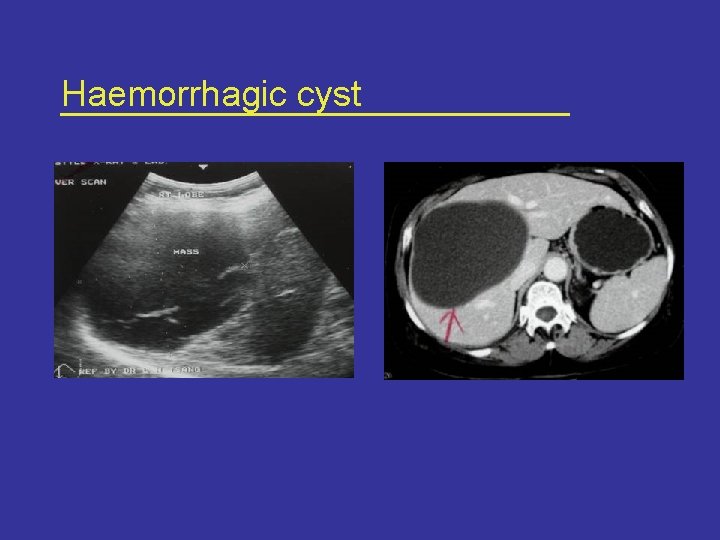

Diagnostic challenge • Pre-operative diagnosis often difficult • Other pathological lesions can mimic clinical and radiological characteristics*: – – – Simple cyst Hydatid cyst Liver abscess Cystic degeneration of liver neoplasm Caroli’s disease Polycystic liver disease *Lewis et al Arch Surg. 123, 563 -8, 1988.

Haemorrhagic cyst